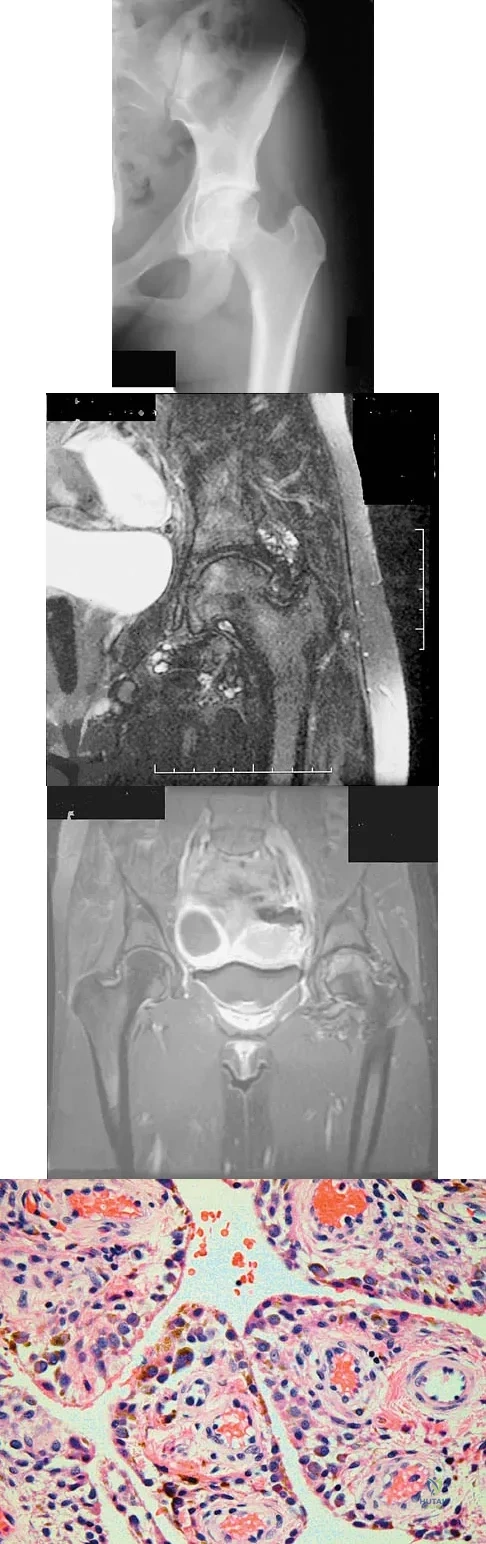

Figures 1a through 1c show the radiograph and MRI scans of a 16-year-old patient who has a painful hip. Examination reveals a significant limp, limited abduction and internal rotation, and severe pain with internal rotation and adduction. A biopsy specimen is shown in Figure 1d. What is the deposited pigment observed in this condition?

Explanation

A 35-year-old patient has right hip pain. Figures 34a and 34b show the coronal MRI scan and the biopsy specimen. What is the most likely diagnosis?

Explanation